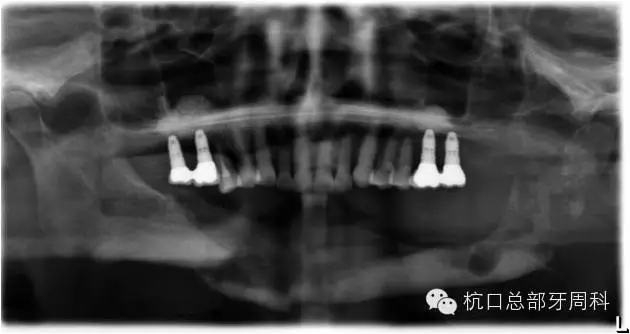

初診時(shí)全景片2011.7

112.webp.jpg

全景片:大范圍火山口樣/彈坑樣骨缺損

CT:左下缺牙區(qū)及部分升支存在骨破壞